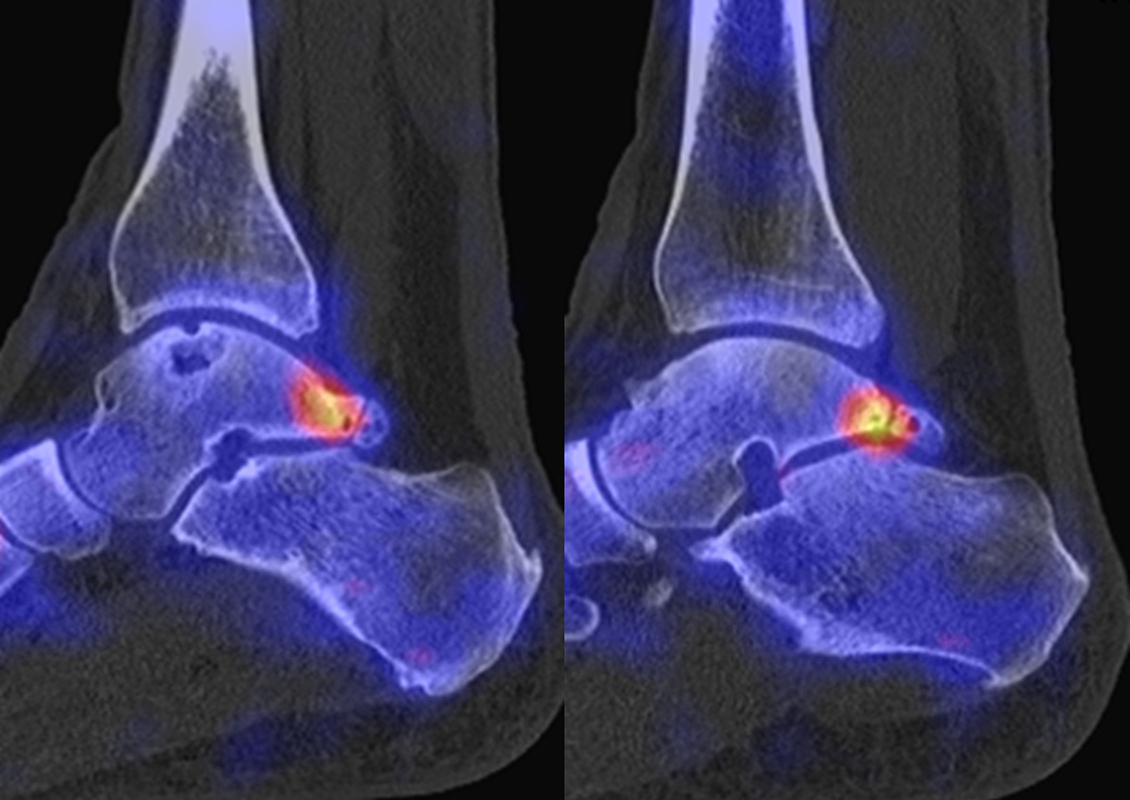

Abbildung 8.1. a bis f.: Patient mit Z. n. OSG-Distorsion vor 8 Monaten und konservativer Therapie. Anhaltende Schmerzen im Bereich des linken Innenknöchels. Im MRT bestand der Verdacht auf eine symptomatische kleine osteochondrale Läsion im medialen linken Talus (Abbildung 8.1. a und c). Zur weiteren Klärung erfolgte eine SPECT/CT 30 Tage später, welche jedoch im Gegensatz zur MRT eine fokale Mehrspeicherung an der tibialen Insertion des Deltabandes nachwies. Die Tatsache, dass die SPECT/CT spezifischer als die MRT symptomatische Bandläsionen detektieren kann wird untenstehend ausführlich thematisiert.

Abbildung 8.2. zeigt den Fall eines Patienten mit Verdacht auf ein knöchernes posteriores Impingement. Es bestanden Beschwerden dorsal bei Plantarflexion und ein Z. n. Distorsion des linken OSG vor 2,5 Jahren. Im MRT 2 Monate vor der SPECT/CT keine wegweisenden Befunde. Im SPECT/CT eindeutige fokal deutliche Mehrspeicherung im Bereich des Processus posterior tali.

Abbildung 8.3.a bis d demonstrieren Bilder einer Patientin mit Z. n. Arthrodese des linken OSG vor 6 Jahren. Das MRT ist bei ausgedehnten Metallartefakten nur bedingt aussagekräftig und weist nicht auf die auffälligen Befunde im SPECT/CT hin. Es bestehen sowohl fokale Stressreaktionen im Bereich eines Os trigonum und lateral im USG.

Abbildung 8.4.a bis d: Bilder einer Patientin mit chronischen Schmerzen im lateralen unteren Sprunggelenk links. Im MRT V. a. akzessorisches Knochenelement. Anamnestisch Beschwerden im Bereich des linken Sprunggelenkes seit 5 Monaten. Zuvor intensive sportliche Betätigung. Unter anderem tägliche atypische Belastung beider Füße durch Hinknien im Rahmen der Tätigkeit als Erzieherin. Diese Patientin hat nebenbefundlich bilaterale Akzessoria bzw. einen beiderseits angelegten Talus secundarius, der linksseitig jedoch nicht für die Symptomatik verantwortlich ist (die Bilder davon werden in Abbildung 3.5. gezeigt). Verantwortlich für die Symptomatik ist ein links posterolateral am Talus atypisches Knochenelement in einer Mulde mit engem Bezug zum unteren Sprunggelenk, DD atypisches laterales Os trigonum oder DD atypische Osteochondrosis dissecans. Die MRT konnte nicht differenzieren, wo die Schmerzursache genau lag. Im SPECT/CT (Abbildung 8.4.b und d) eindeutig fokale Mehrspeicherung im Bereich des atypischen Knochenelementes. Intraoperativ bestand der Aspekt einer Osteochondrosis dissecans.